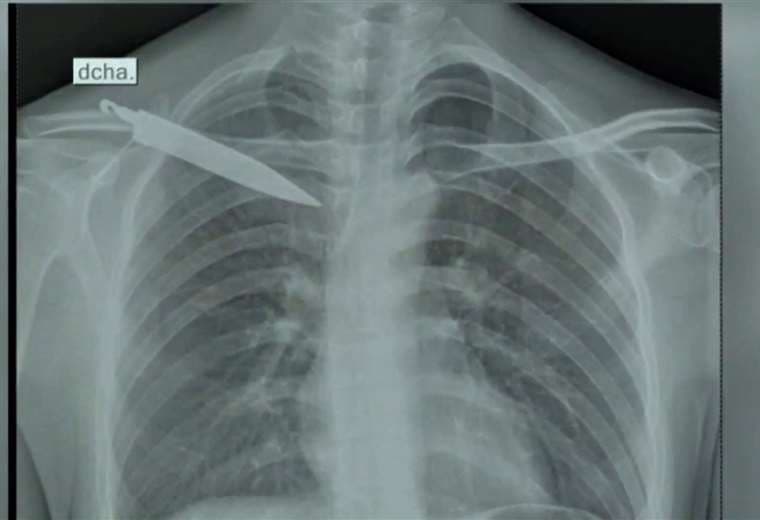

Médicos peruanos se llevaron una gran sorpresa al encontrar un objeto punzocortante, de más de 10 centímetros de largo, incrustado en la espalda de un joven de 28 años; pero mayor fue el asombro al enterarse de que el objeto había estado alojado en su cuerpo por casi un mes (ver video adjunto).

En el hospital de Pangoa, y tras una evaluación, se ordenó que Tarazona pasará por Rayos x, llevándose así la sorpresa: había un cuchillo en su espalda.